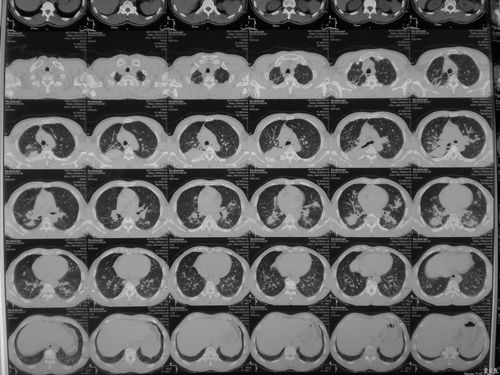

尘肺的影像表现及鉴别诊断

尘肺病ct影象图片

尘肺的ct图片

尘肺一期的ct图片早期

尘肺早期ct报告

尘肺ct

尘肺二期ct报告单图片